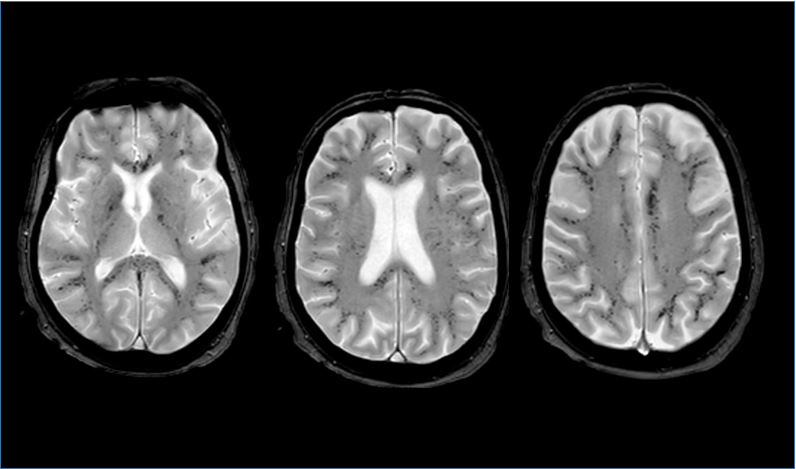

Cortes axiales en ponderación T2 FFE de una RM cerebral realizada 41 días tras el ingreso en la UCI. Numerosos microsangrados están involucrando difusamente la substancia blanca yuxtacortical, el cuerpo calloso y las cápsulas internas. La sustancia blanca profunda y periventricular así como la sustancia gris están respetados. Estas micro hemorragias no son visibles en las otras secuencias (T1, FLAIR, difusión)

En pacientes en cuidados intensivos se ha descrito un patrón distinto de distribución de microhemorragias cerebrales que afecta la sustancia blanca yuxtacortical del cuerpo calloso y de cápsulas internas, de forma extensa, como en nuestro paciente. La causa última de estas estas hemorragias petequiales no se conoce, pero la patogénesis puede implicar la hipoxia, ya que la distribución es similar a las descritas con la exposición a gran altitud y el síndrome de distrés respiratorio agudo y todos los pacientes con esta distribución de las microhemorragias presentan en común un fallo respiratorio.